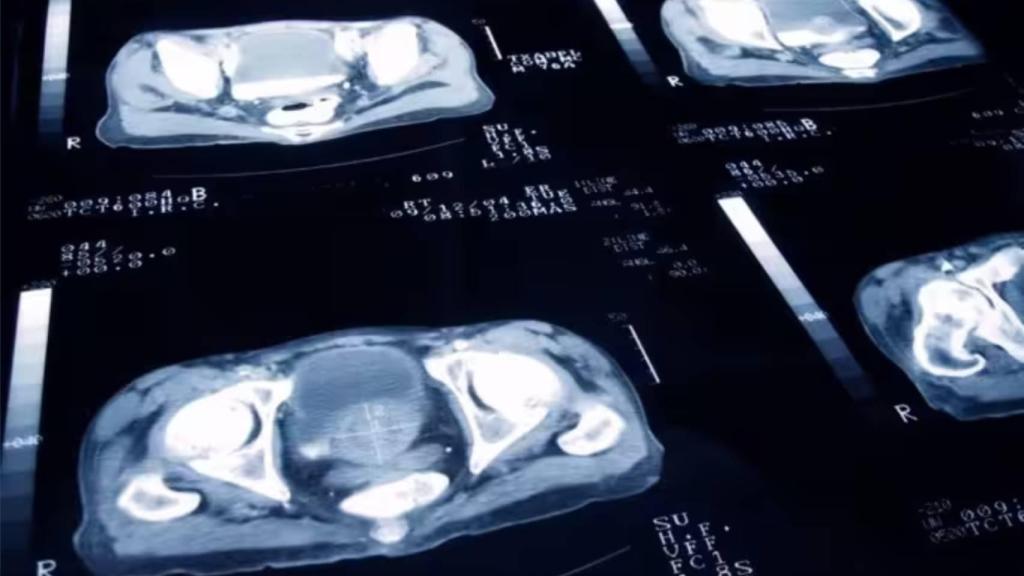

Próstata